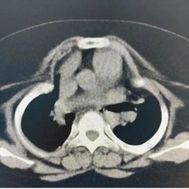

ATD can be classified into two types. Type I ATD is characterized by overall narrowing of the thoracic cage, with both the transverse and anteroposterior diameters markedly reduced compared with a normal chest. Type II ATD is a distinct form of thoracic narrowing, primarily characterized by extensive bilateral depressions of the lateral chest walls. The depressions involve multiple ribs and often extend to the costal arches.

The constriction of the chest severely impairs respiratory function, making ATD a critical condition. Most patients succumb to hypoxia soon after birth.